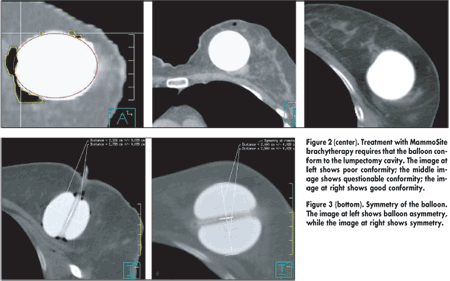

All patients underwent CT imaging to measure balloon diameter and to confirm adherence to three strict inclusion criteria, he said. The first was adequate skin spacing, defined as at least 5 mm but ideally more than 7 mm (see Figure 1). The second was adequate conformity of the balloon to the lumpectomy cavity, assessed subjectively and, in questionable cases, objectively; by objective assessment, conformity was acceptable if the percentage of air and seroma with respect to PTV (planning target volume) was less than 10% (see Figure 2). The third was adequate symmetry of the balloon, defined as achievement of radial measurements within 2 mm of each other (see Figure 3).